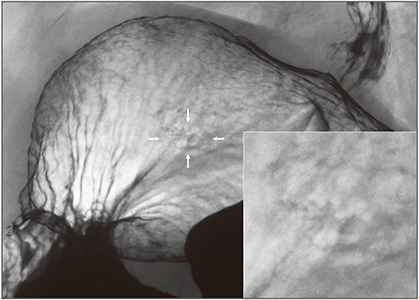

octaveによる胃癌の症例画像を提示する。図10は、体中部後壁に不規則な輪郭を示すはじき像が認められる例である。近接して表面模様を見てみると、隆起部と周囲粘膜の模様はよく似ている。最終病理診断は、0-IIa+IIc型、粘膜下層に浸潤する25×10mmの分化型癌であった。図11は、腹臥位二重造影第1斜位像で、噴門部に近い体上部前壁に粘膜集中が観察された例である。周囲正常粘膜と比べて病変部粘膜には濃淡の差が認められ、その輪郭には微細な線状陰影が描出されていた。0-Ⅱc型、粘膜下組織の浅層に浸潤する45×21mmの分化型癌であった。図12は、胃角部前壁小彎のはっきりとした凹凸が目立つ病変である。漿膜外に浸潤する未分化型の3型進行癌であった。

図10 0-IIa+IIc型、25×10mm、tub2、SM2

図11 0-IIa+IIc型、45×21mm、tub1>tub2、SM2、Ul(+)